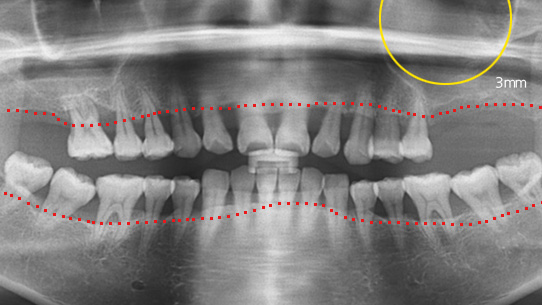

잇몸뼈가 녹아내려 임플란트 12개 진단을 받고 내원한 환자, 고운미소에서 치주치료를 시행한 결과 전치부 잇몸이 개선되어 발치 하지 않고

크라운으로 수복하였고, 어금니에 6개의 임플란트를 식립하였습니다.